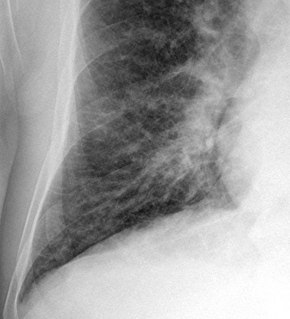

Chest X-rays are frequently used to aid in the diagnosis of CHF. In a person who is compensated, this may show cardiomegaly (visible enlargement of the heart), quantified as the cardiothoracic ratio (proportion of the heart size to the chest). In left ventricular failure, there may be evidence of vascular redistribution ("upper lobe blood diversion" or "cephalization"), Kerley lines, cuffing of the areas around the bronchi, and interstitial edema. Ultrasound of the lung may also be able to detect Kerley lines.[38]

Congestive heart failure with small bilateral effusions.

Kerley b lines.